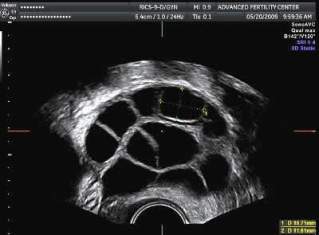

The other day I cut into a lemon to make the lemon-egg sauce used in many Turkish recipes. And this was the cross section –

a throw-back to my left ovary in its artificially hyper-stimulated heyday. Follicles are not exactly round and perfect, as one would otherwise think. They’re smooshed together like a bunch of sleeping hamsters, with forms malleable enough to manage the crowded quarters prior to egg retrieval. During an IVF cycle, daily – sometimes twice daily – follicle-stimulating hormone injections will hopefully yield a dozen 15-20mm follicles in each ovary.